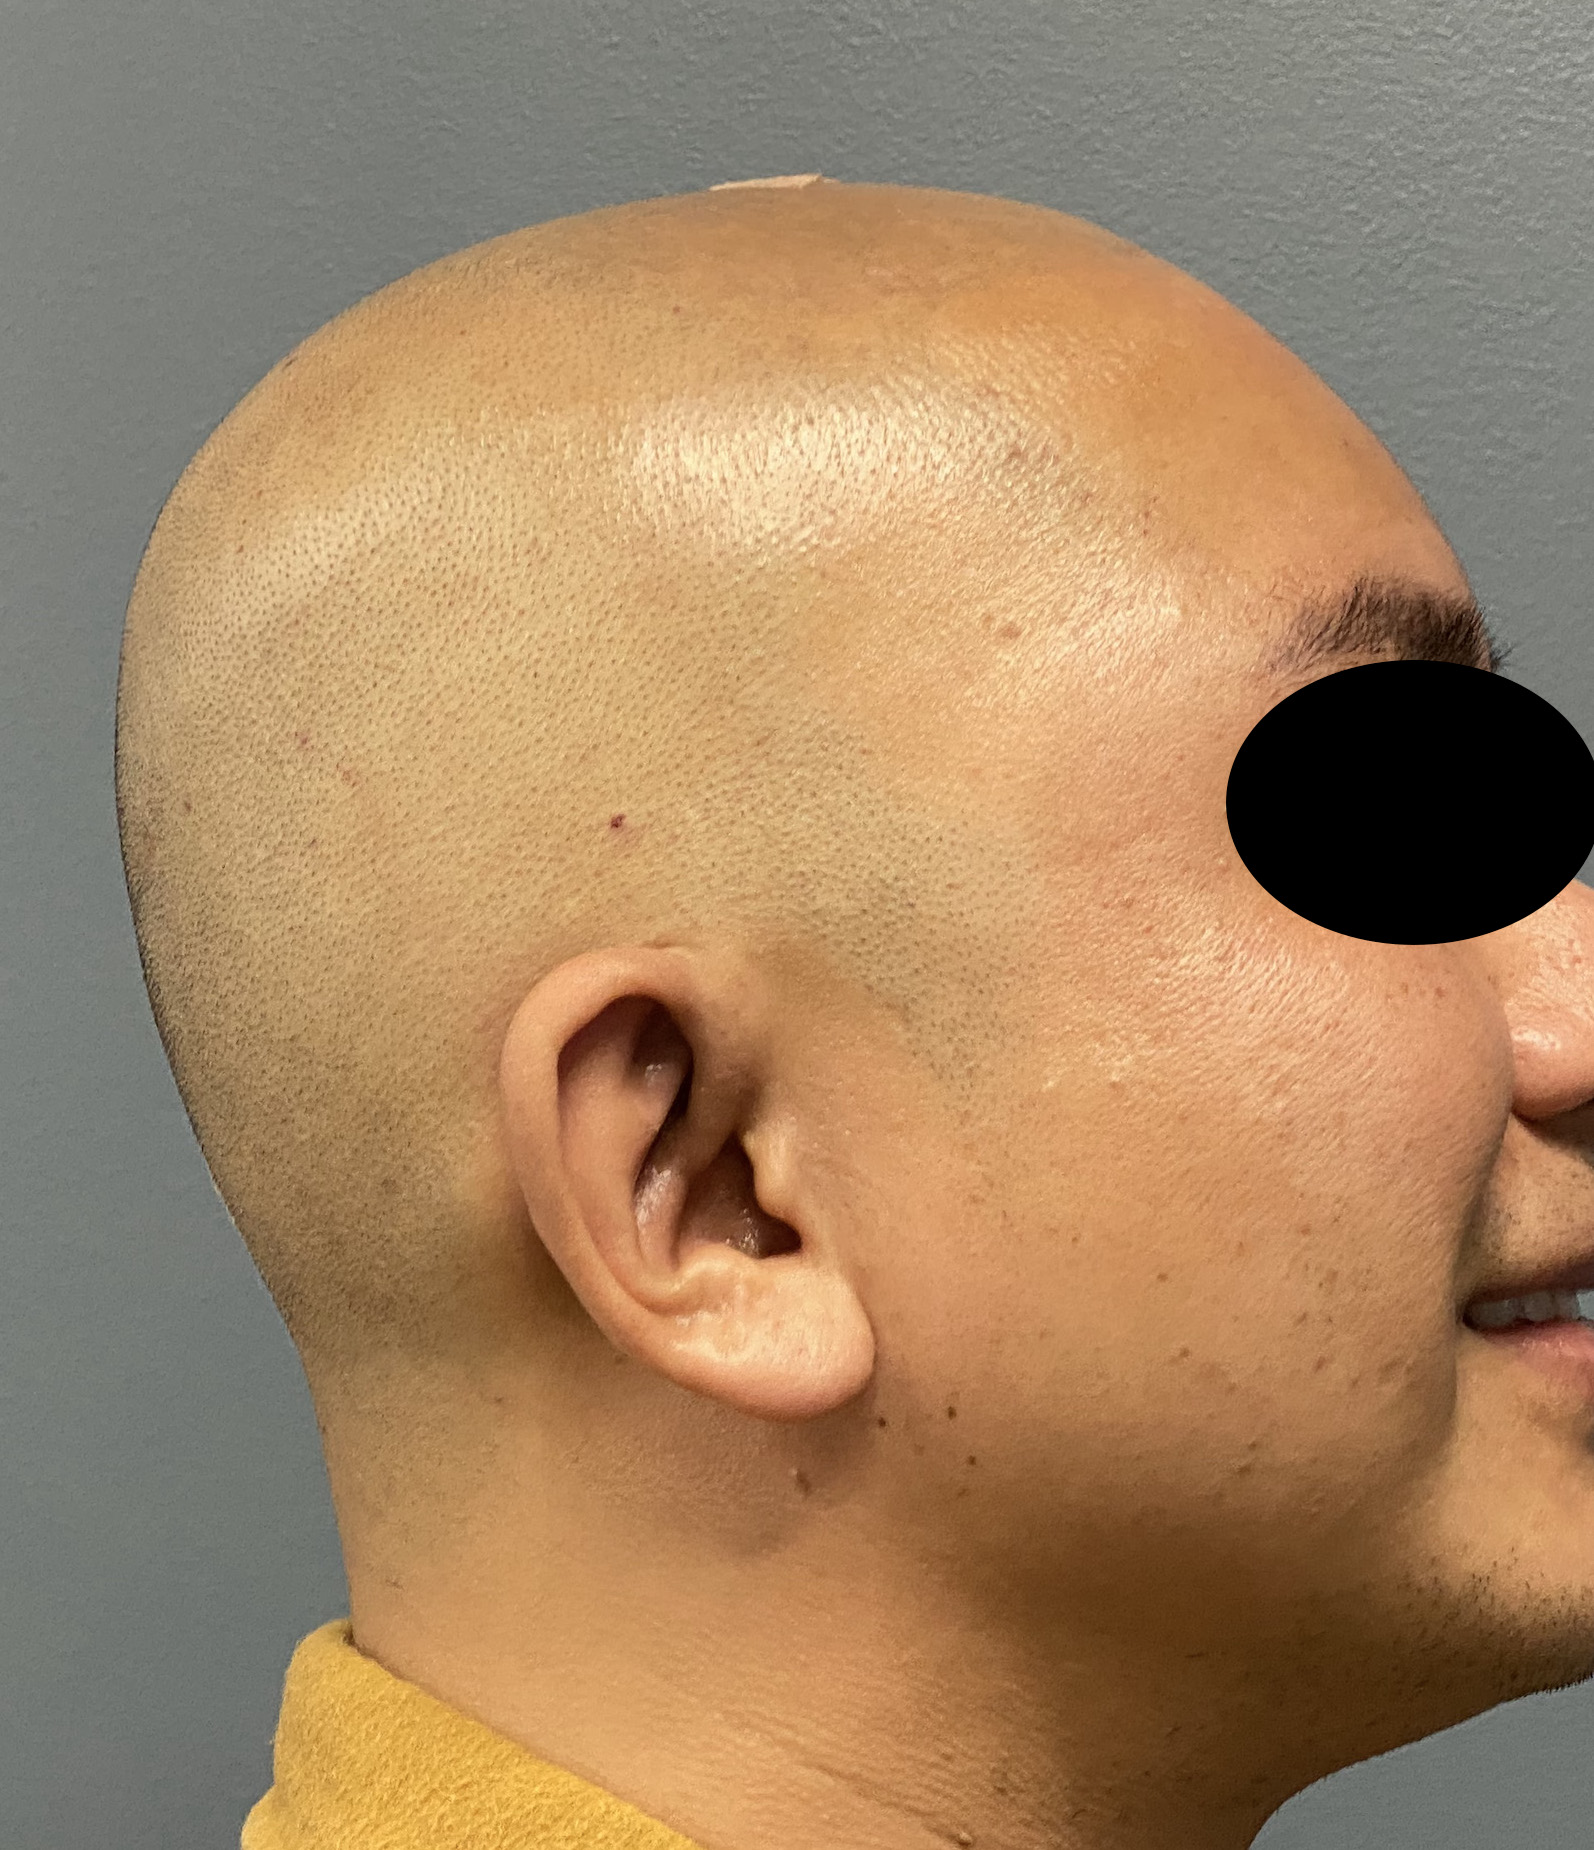

Desire for reshaping of an asymmetric flat back of the head in a shaved head male.

A combined back of the head reshaping procedure was done with a custom skull implant, sagittal ridge reduction and a right temporal muscle reduction.

Desire for reshaping of an asymmetric flat back of the head in a shaved head male.

A combined back of the head reshaping procedure was done with a custom skull implant, sagittal ridge reduction and a right temporal muscle reduction.